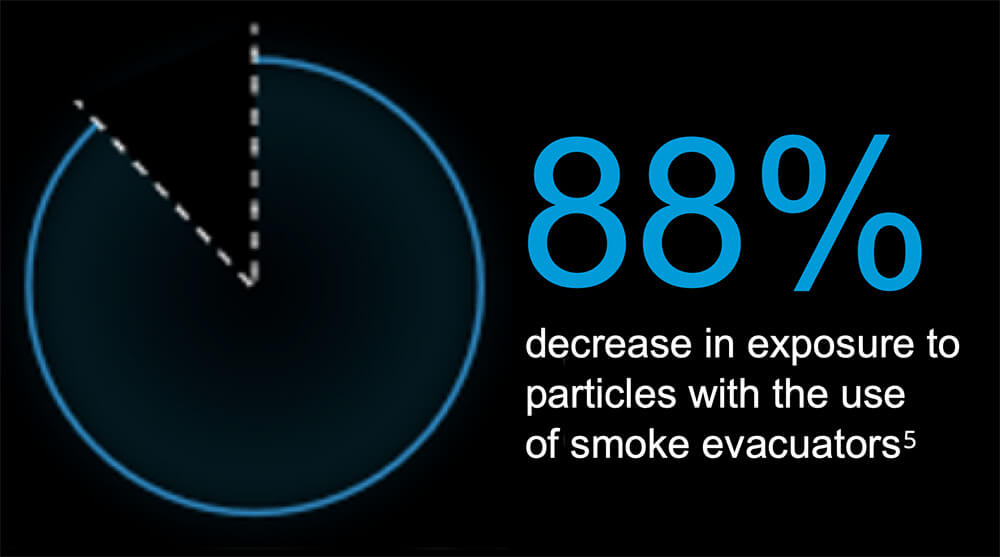

5Karjalainen M, Kontunen A, Saari S, Rönkkö T, Lekkala J, Roine A, Oksala N. The characterization of surgical smoke from various tissues and its implications for occupational safety. PLoS One. 2018 Apr 12;13(4):e0195274. doi: 10.1371/journal.pone.0195274. PMID: 29649244; PMCID: PMC5896939